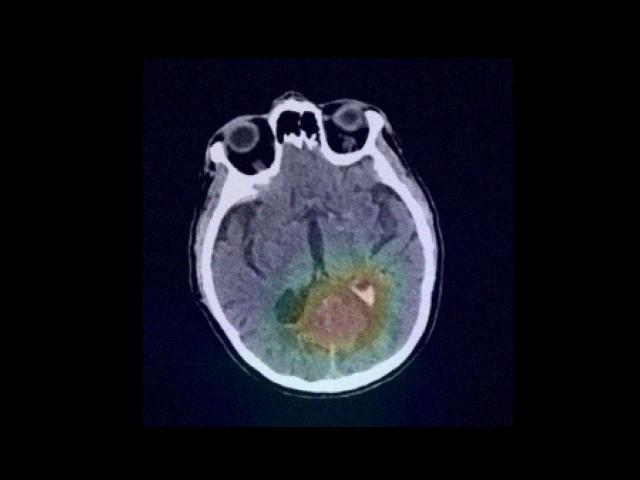

Sample Gallery